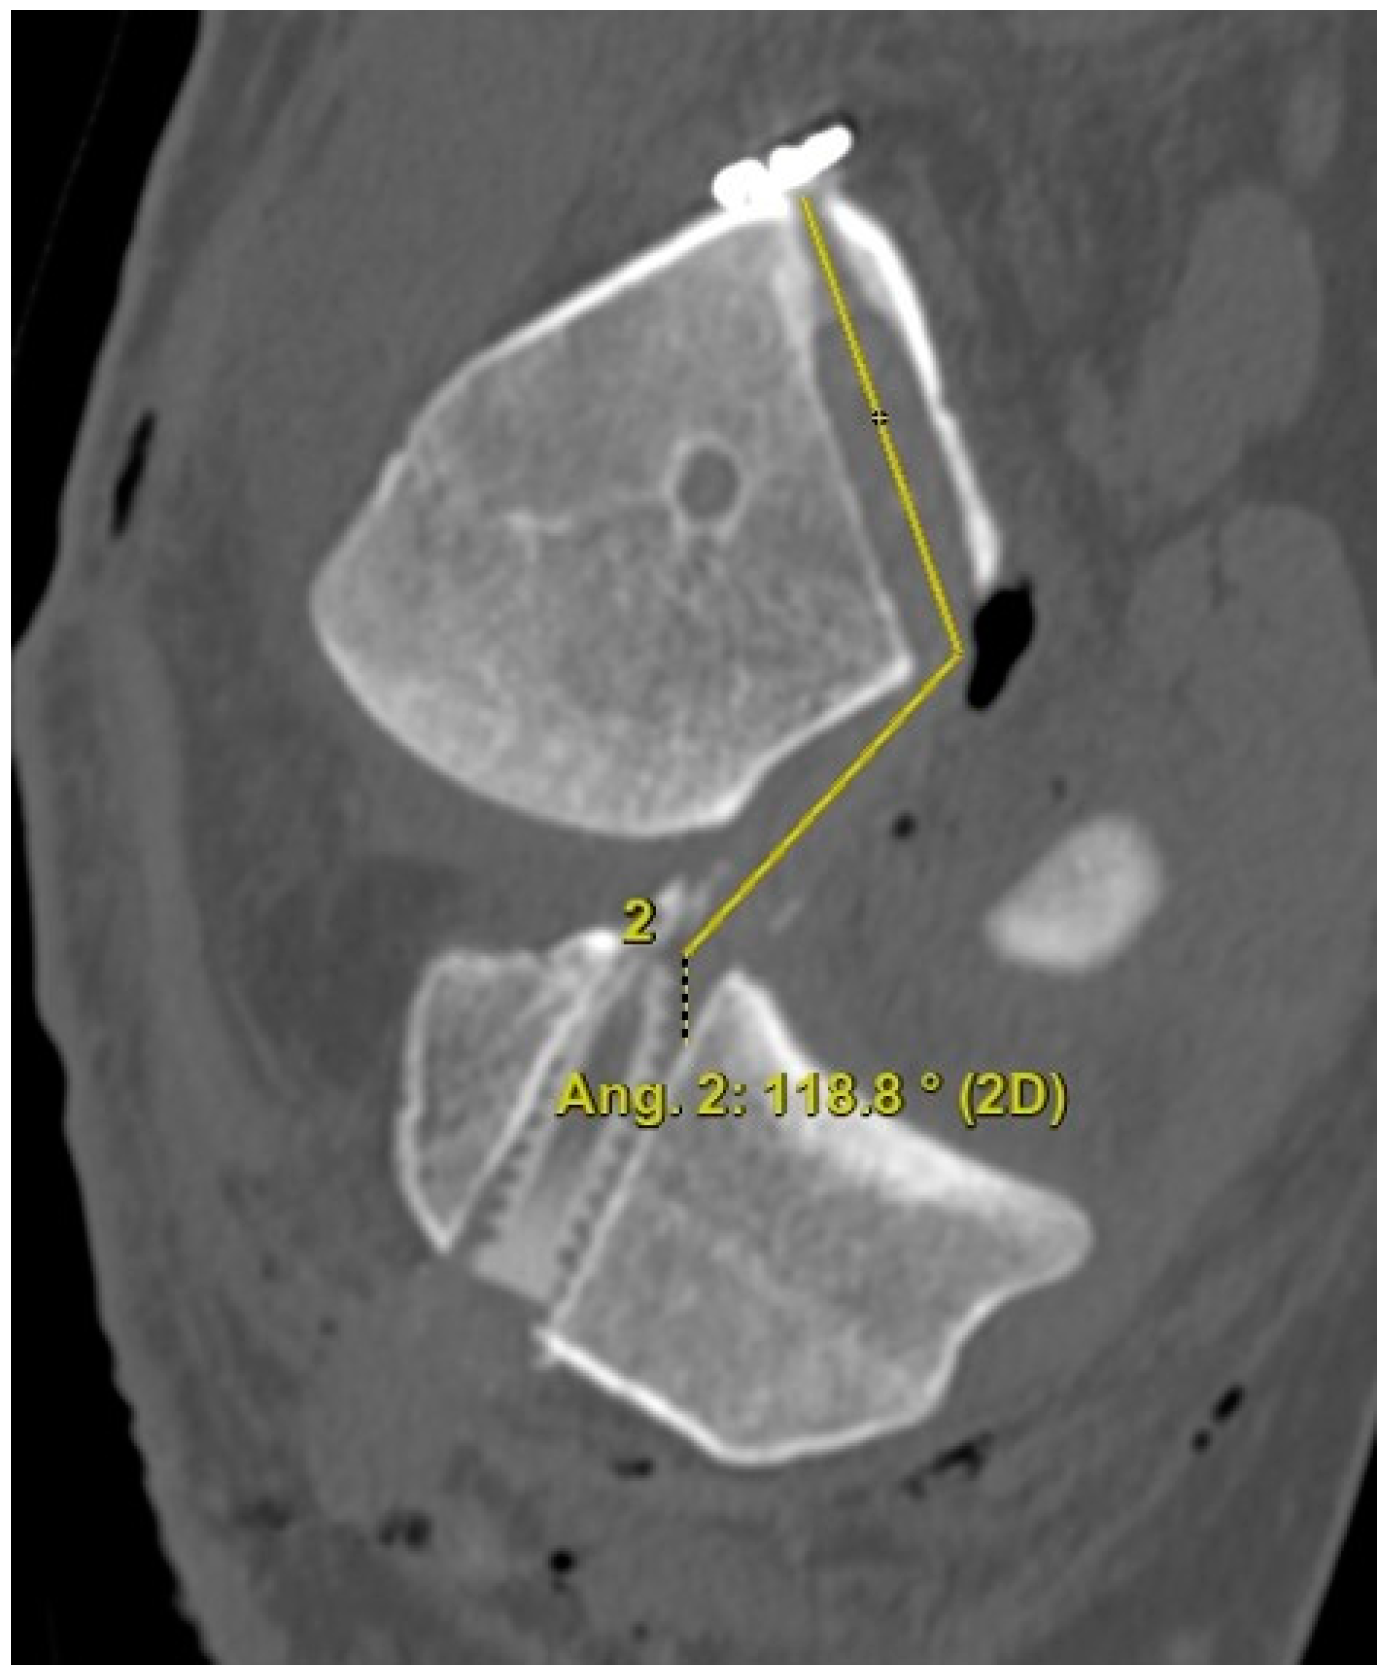

The 3D CT scans were imported into 3D software (AW Sever 3.2 PACS system, GE Healthcare; Chicago, IL, USA) for the assessments of the femoral graft bending angle and femoral tunnel length. The femoral graft bending angle was defined as the angle formed by the longitudinal axis of the femoral tunnel and the line connecting the intra-articular aperture of the tibial tunnel and the intra-articular aperture of the femoral tunnel (Figure 3). The femoral tunnel length was defined as the distance between the center of the extra-articular aperture of the femoral tunnel and the center of the intra-articular aperture of the femoral tunnel in a plane where the entire femoral tunnel could be viewed (Figure 4). Posterior wall breakage of the femoral tunnel was also checked.

Figure 3.

The femoral graft bending angle is defined as the angle formed by the longitudinal axis of the femoral tunnel and the line connecting the intra-articular aperture of the tibial tunnel and the intra-articular aperture of the femoral tunnel.

Regarding the femoral tunnel location, it was located at 29.7 ± 4.4% in the posterior to anterior (deep to shallow) direction and at 24.1 ± 5.9% in the proximal to distal (high to low) direction. The mean femoral graft bending angle was 113.9 ± 5.7°, and the mean femoral tunnel length was 35.2 ± 3.1 mm (Table 3). There were no cases of a femoral tunnel length <30 mm because the guide pin was redirected for those <30 mm while making the knee joint flexion to approximately 110°. Posterior wall breakage was observed in five patients (8.3%). In the MRIs, the mean coronal graft inclination was 69.2 ± 4.7°, and the mean sagittal graft inclination was 52.4 ± 4.6° (Table 3). The mean posterior tibial slope 241 was 7.9 ± 3.5, and there was no posterior tibial slope of more than 12°.